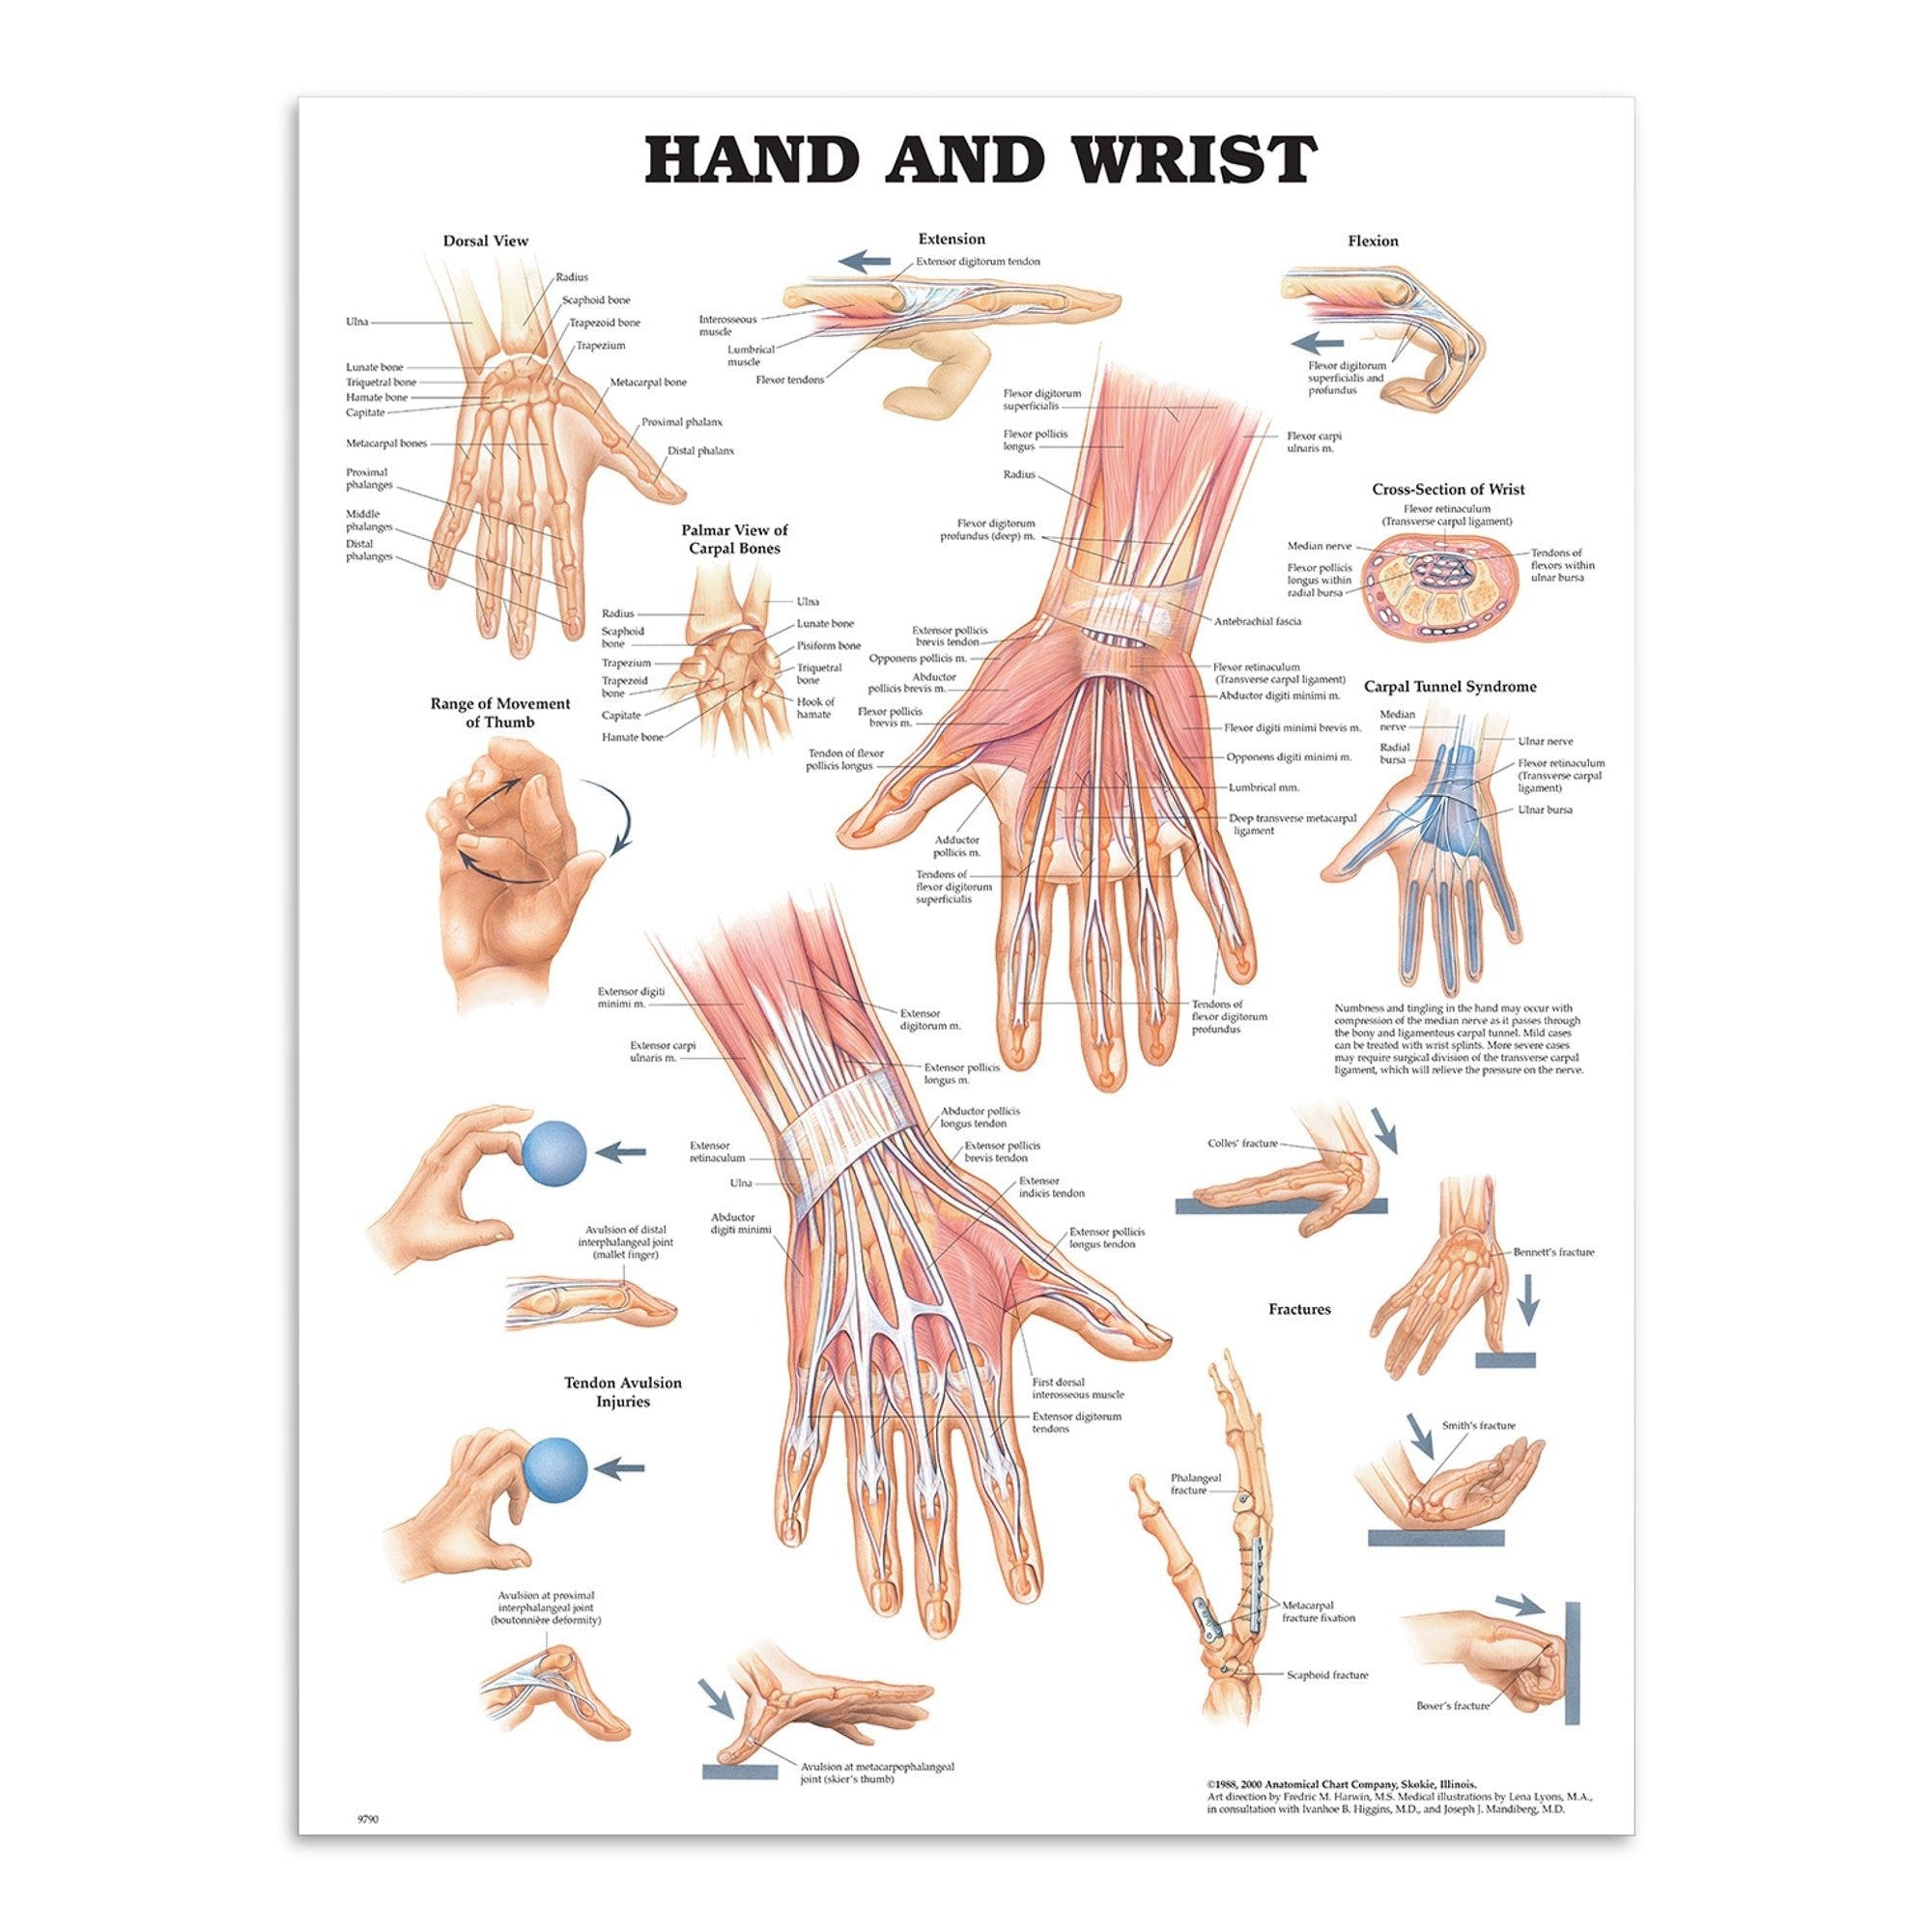

Muscle posters

Muscles provide movement to the musculoskeletal system, and their origins, insertions and lodges are clinically important for every healthcare professional. That is why we at eAnatomi have both developed and designed our own anatomy posters, which provide the ultimate overview of all the muscles of the body. On this page you can find both our own posters and posters from other manufacturers. We offer posters in several different languages such as pure Latin, Danish, English and Swedish, etc.